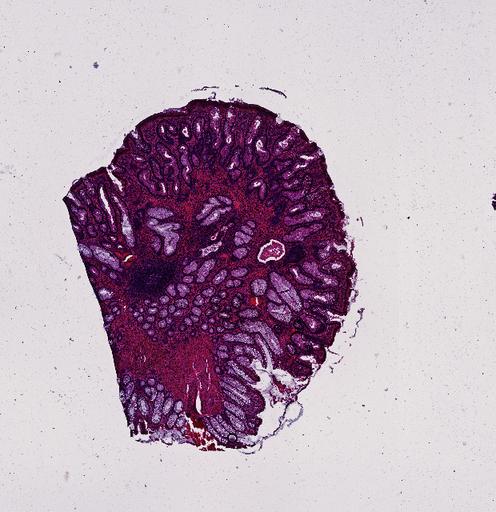

High‑resolution three‑dimensional (3D) tissue atlases promise to redefine how we study cellular architecture‑function relationships in human tissues. Large-scale consortia such as the Human Bimolecular Atlas Program (HuBMAP) systematically build detailed 3D organ maps by profiling serial tissue sections with single-cell spatial technologies. However, an accurate and efficient reconstruction method that can handle atlas-scale datasets remains elusive. We introduce Space-map, an open-source method that integrates single‑cell coordinates with optional histological image features to assemble serial sections into 3D models. Space‑map combines multi‑scale feature matching with large‑deformation diffeomorphic metric mapping, delivering global reconstructions while preserving local micro‑anatomy. To demonstrate the capability of Space-map, we generated a serially sectioned spatial transcriptomics (Xenium, ~2.9M cells) dataset and a spatial proteomics dataset (CODEX, ~2.4M cells). Applying Space-map to these single-cell spatial maps, we built three 3D models for both diseased (colon polyp) and reference colon tissues. These high-resolution 3D models showcase the intricate structure of the human colon across different states. Space-map is fast and highly efficient. We demonstrated its performance and accuracy using in‑house and public datasets. The result shows that Space‑map is 10 times faster and ~2‑fold more accurate than PASTE and STalign, making 3D atlas reconstruction more accessible. Our study provides a new robust and user-friendly software available at https://github.com/a12910/spacemap that can be easily applied for constructing molecular 3D tissue maps of human organs at single-cell resolution.